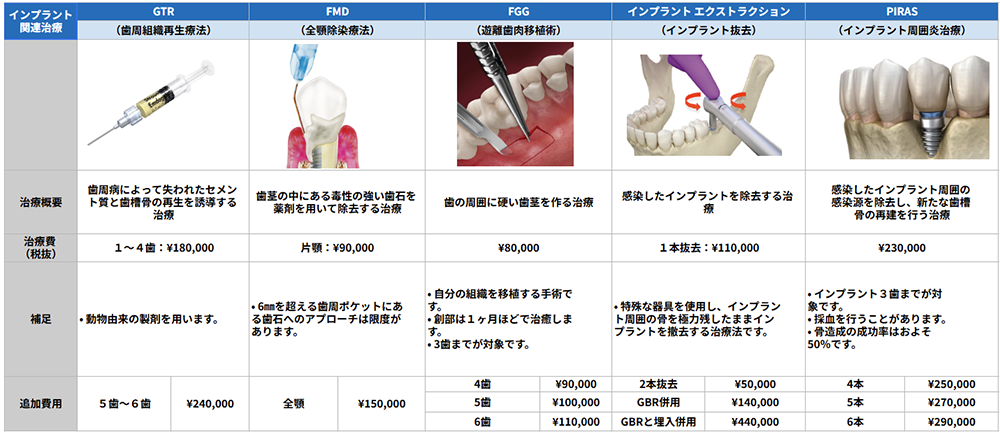

歯周病関連治療一覧表

インプラント関連治療一覧表